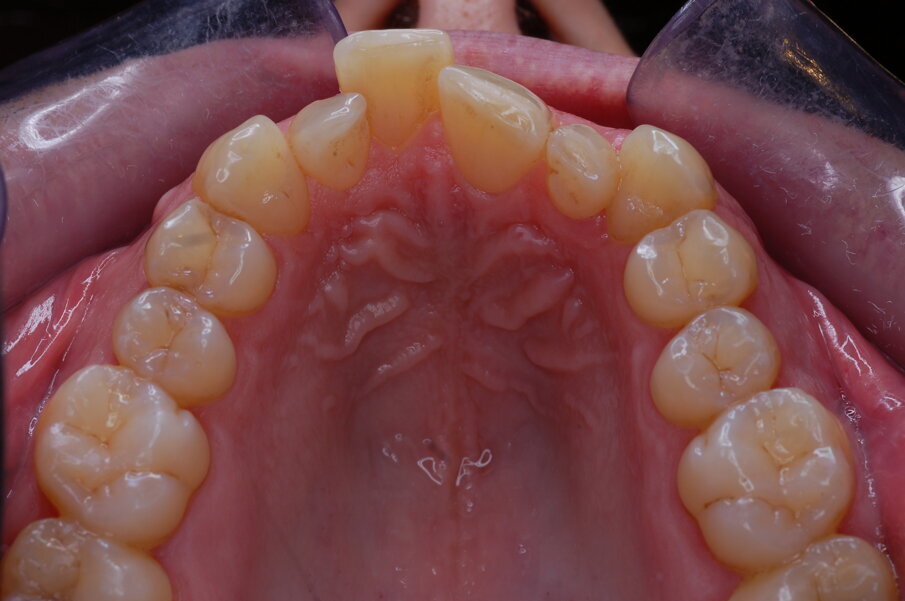

Risultati del trattamento Le fotografie extraorali post-trattamento hanno mostrato il miglioramento dell’estetica del sorriso (Figg. 51-58). È stata ottenuta una solida occlusione bilaterale di Classe I con overjet e overbite normali. Le arcate dentali erano ben allineate e livellate e anche la grave rotazione del secondo premolare mandibolare sinistro è stata corretta solo con gli allineatori. La valutazione cefalometrica post-trattamento (Fig. 59) ha mostrato un miglioramento della posizione anteroposteriore degli incisivi mandibolari (Li-APog: 2,21 mm), pur mantenendo l’altezza facciale (altezza facciale inferiore: 53,12°; asse facciale: 83,96°; Tab. 1). La radiografia panoramica mostrava che la radice dell’incisivo laterale mandibolare destro era stata raddrizzata dall’ausiliario HAT, senza alcun importante riassorbimento radicolare, raggiungendo un buon parallelismo con i denti adiacenti (Fig. 60). I terzi molari mandibolari impattati erano ancora presenti perché il paziente si rifiutava di estrarli.

Figg. 51-58_Fotografie facciali e intraorali post-trattamento.